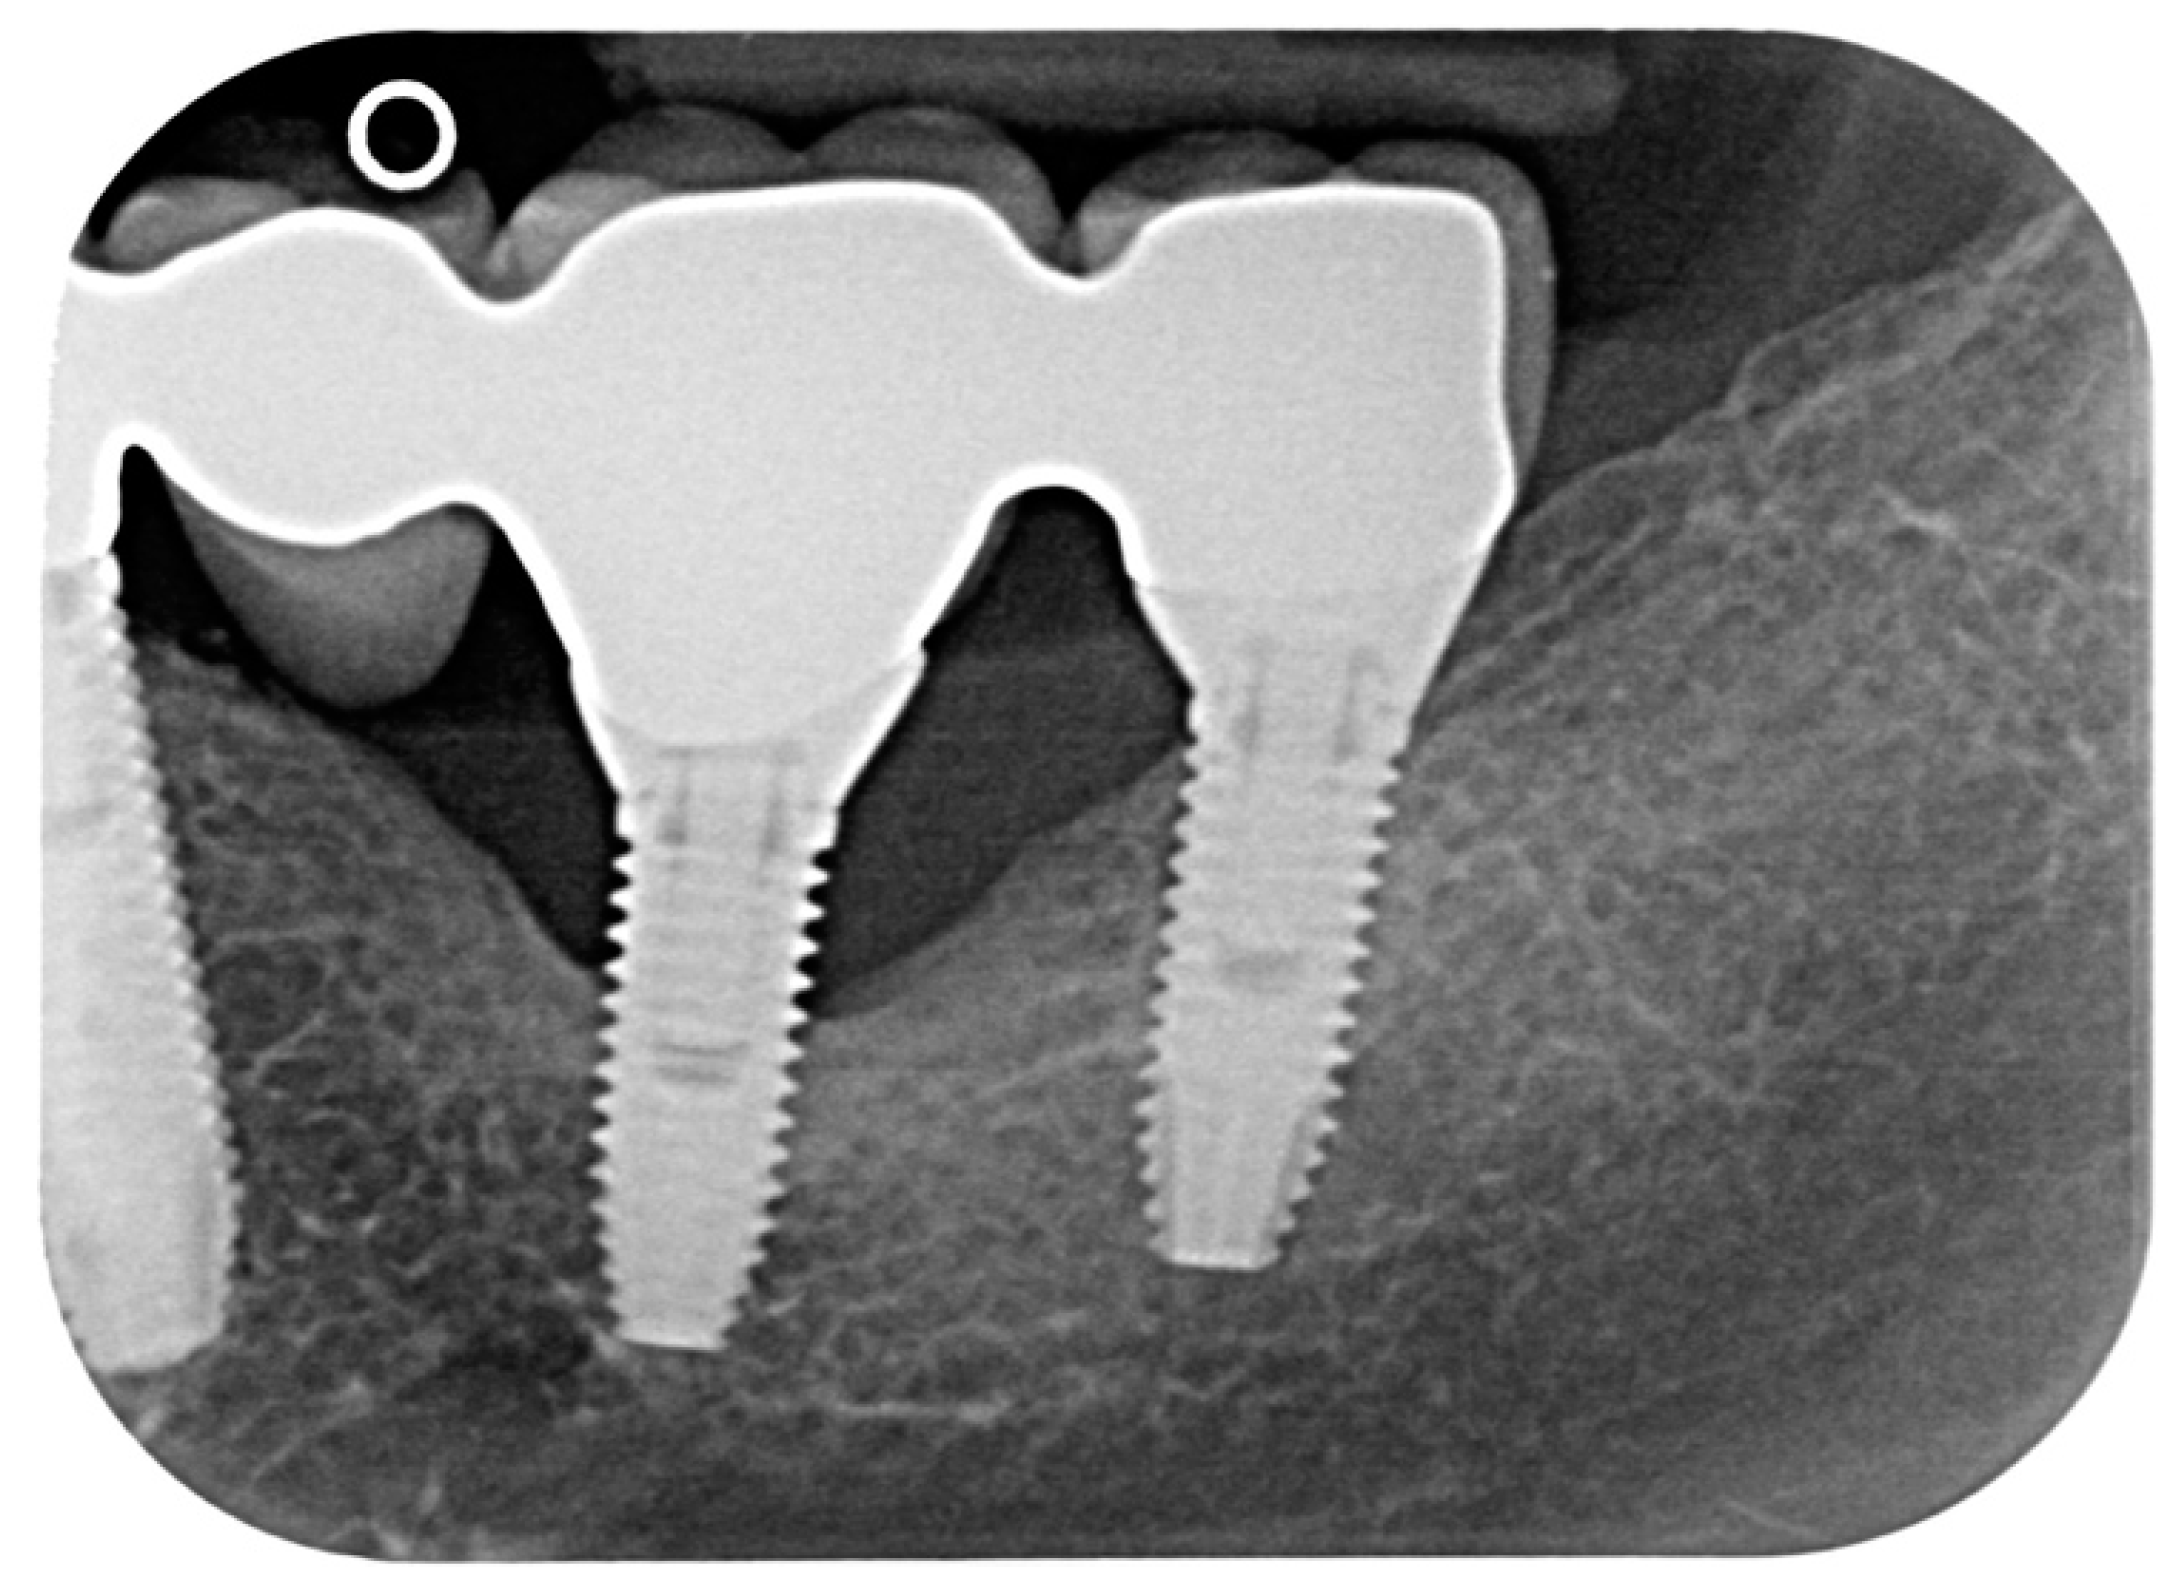

A total of 23 cases of peri-implantitis (patient-level) were registered, representing an overall prevalence of 11.3%. Only one diabetic patient (type 2) developed peri-implantitis (5.3%) whereas one subject with type 1 diabetes experienced multiple implant failures due to a failure of osseointegration. Figure 1 and Figure 2 show radiographic evidence of peri-implantitis in one diabetic (Figure 1) and one non-diabetic patient (Figure 2). Figure 1 and Figure 2 show radiographic evidence of peri-implantitis in one non-diabetic (Figure 1) and one diabetic patient (Figure 2). A clinical image of the same diabetic patient is represented in Figure 3.

Figure 1.

Periapical radiograph of one case of peri-implantitis in a non-diabetic subject.